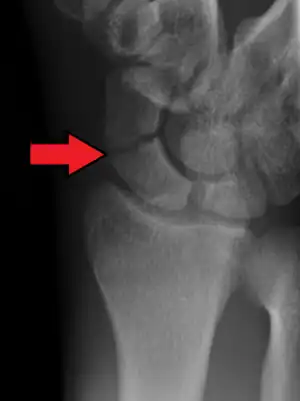

Scaphoid fractures are often diagnosed by PA and lateral X-rays. However, not all fractures are apparent initially.[7] Therefore, people with tenderness over the scaphoid (those who exhibit pain to pressure in the anatomic snuff box ) are often splinted in a thumb spica for 7–10 days at which point a second set of X-rays is taken.[7] If there was a hairline fracture, healing will now be apparent. Even then a fracture may not be apparent. A CT Scan can then be used to evaluate the scaphoid with greater resolution. The use of MRI, if available, is preferred over CT and can give one an immediate diagnosis.[9] Bone scintigraphy is also an effective method for diagnosis fracture which do not appear on Xray.[10]